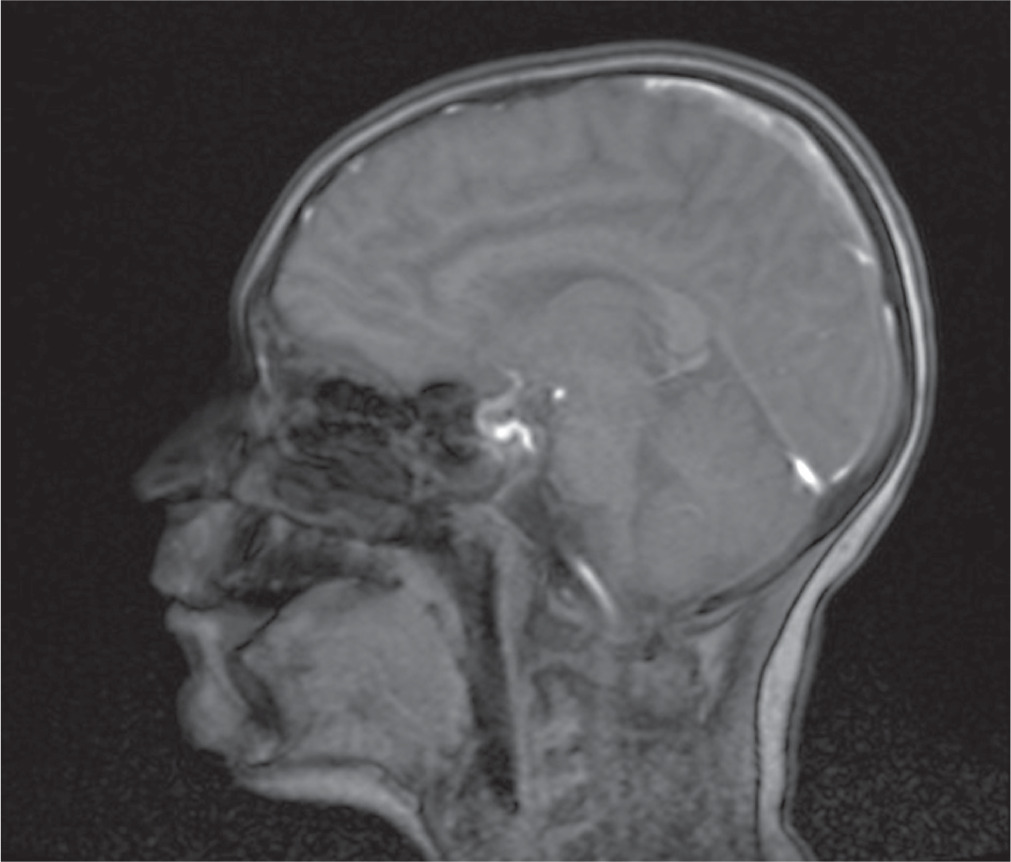

An 11-year-old male patient, without perinatal abnormalities, properly developing, diagnosed at age of 4 with type 1 diabetes mellitus treated with the use of insulin pump was admitted to the Pediatric Neurology Department because of multiple incidents of seizures. The history of his antidiabetic treatment showed lack of control of the disease, which led to chronic hyperglycemia (at admission HbA1c % was 8.1%) throughout the whole duration time of diabetes, despite gradual increasing doses of insulin. Thus, his mother was instructed to increase mealtime insulin dose. During the last appointment in the day-care diabetic unit before the hospitalization the total daily insulin dose was calculated and it was 48 units per day (1.2 unit/kg/day). Due to recuring incidents of symptomless hypoglycemia, measured with glucometer, mostly at night and after physical activity, CGM system was provided. Afterwards, despite of multiple hypoglycemia (up to 20 mg/dl) alarms parents did not adjust the insulin intake, which led to severe hypoglycemia and boy was found unconscious by his mother. The blood glucose level on the glucometer was 35 mg/dl. The last recorded value by CGM was 65 mg/dl. Due to presenting severe seizures and trismus oral glucose intake was not possible, so patient’s mother called the ambulance. He was given intravenous glucose by the ambulance service without recovering consciousness or other improvement of patient’s state. The patient was assessed to have 5 points in the Glasgow Coma Scale, and subsequently was intubated and given an intravenous infusion of glucose and midazolam without any improvement. The boy was admitted to the Intensive Care Unit. Laboratory examination of cerebrospinal fluid did not reveal any features of infection or inflammation. Head CT and chest CT were performed and revealed cerebral edema, hypo-dense areas and obliteration of temporal lobes of the brain as well as inflammatory features in the left lung. He was provided with mannitol, diuretics, broad-spectrum antibiotics (tazobactam and piperacillin), benzodiazepines and parenteral nutrition. The patient was treated in the ICU for 4 days, after which he was extubated and transferred to the Diabetology Clinic. CSF autoantibodies tests were performed and due to the similarity of clinical symptoms to autoimmune encephalitis a 5-days intravenous immunoglobulin treatment was administered. However, results of autoimmunobodies tests did not confirm autoimmune encephalitis. Go Brain MRI was performed and showed in both cerebral hemispheres, symmetrically, elevated white matter signal, mainly in the subcortex and cortex of the frontal and occipital and parietal lobes with features of diffusion restriction. Similar changes were seen in the posterior branches of the internal capsule (Fig. 1). The whole image indicated hypoglycemic encephalopathy without features of cerebral edema. EEG revealed generalized slow brain activity, without obvious epileptiform. Due to severe neurological condition he was transferred to the Pediatric Neurology Department. The patient was conscious but without logical contact. He was in constant psychomotor restlessness, did not follow commands and did not cooperate during the examination. Control brain MRI was performed and showed regression of previously described features. After stabilization of the patients state he was discharged. In the next two months, due to the brain damage caused by a hypoglycemic episode the patient developed epileptic seizures. After the first seizure with the morphology of a generalized convulsion he was transported to the hospital. Infection, dehydration, hypoglycemia or other causes that could have led to seizures were excluded. Since then the patient has 1–2 seizures per day presenting with atonia, right upper limb clonus and clonus of lower limb, which resolve spontaneously. Once every few months he has a generalized tonic-clonic seizure. Since the beginning of the epileptic seizures, antiepileptic treatment was induced. He was provided with a variety of antiepileptic drugs, such as carbamazepine, oxcarbazepine, valproic acid, lamotriginum, primidonum, lacosamidum, clobasamum, vigabatrinum and sultiamum. Currently, he is treated with clobasamum, sultiamum and lacosamidum. Unfortunately, none of the aforementioned drugs yielded with satisfactory results so far and the patient is still suffering from drug-resistant epilepsy. The patient is under regular control of day care diabetic unit. The basal insulin dose was decreased and mother adequately adjusts insulin dose according to the glycemia level. That allowed to obtain satisfactory control of glycemia and lack of severe incidents of hypoglycemia. Nonetheless, such serious course of hypoglycemia significantly affected patient’s general state and development. Before this serious event he was properly developing and functioning boy and currently he is intellectually disabled to a great extent.

It is important to acknowledge the importance of MRI imagining, while dealing HE. MRI reveals diffuse abnormal intensity in cortex and basal ganglia region. Extensive lesions observed in MRI scanning may predict serious neurological outcomes. Moreover, the degree of lesions may also affect the degree of presenting neurological symptoms [7].

In our patient’s case lesions were observed in occipital and parietal lobes of the brain, which is a typical localization of the MRI findings among patients with HE, as these regions are relatively more sensitive to hypoglycemia [7].